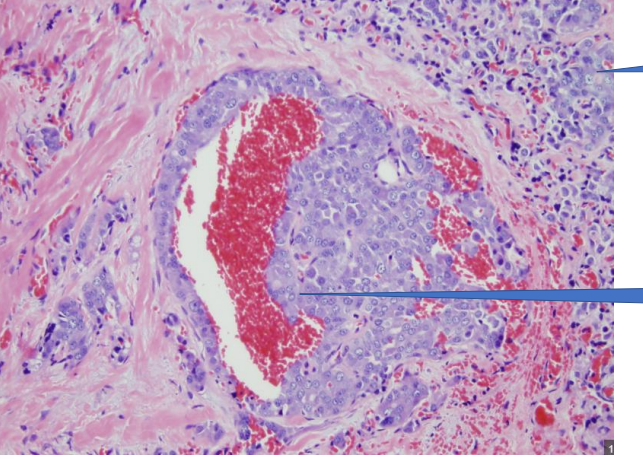

1- Blood vessel

2- Vascular invasion

1- Malignant Tumor

Malignant Tumor

Vascular invasion